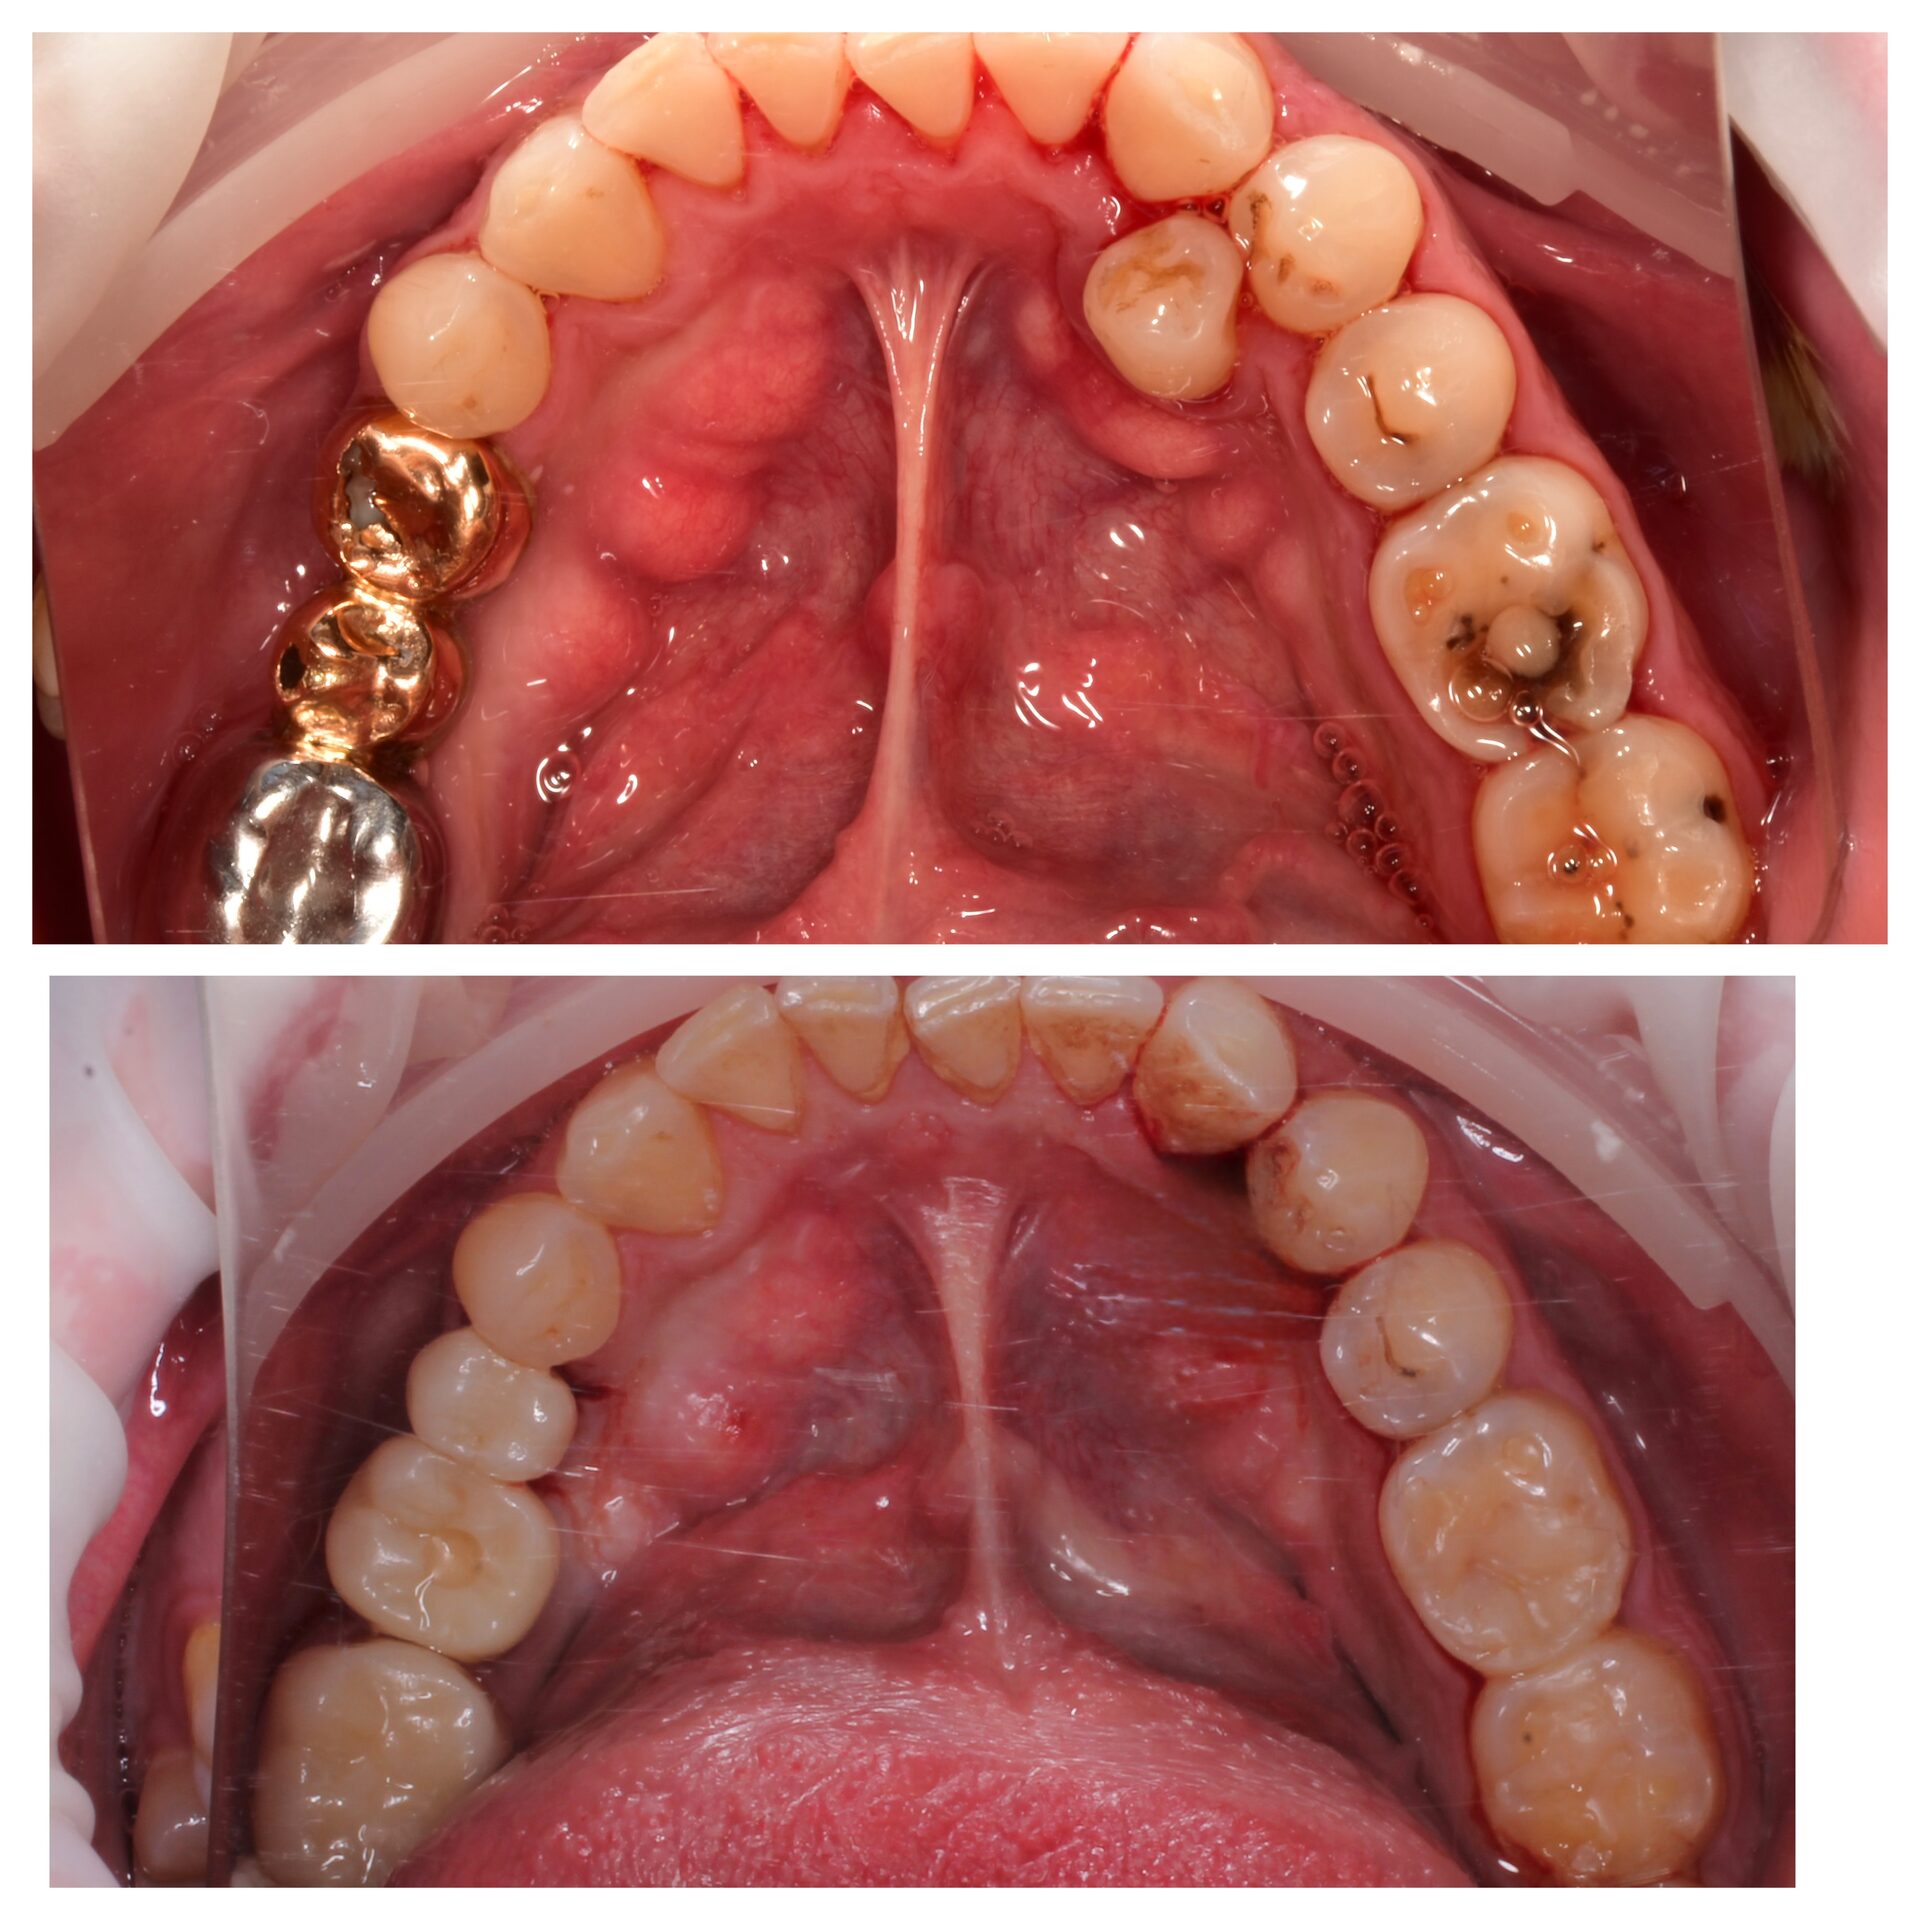

Лечение кариеса под микроскопом